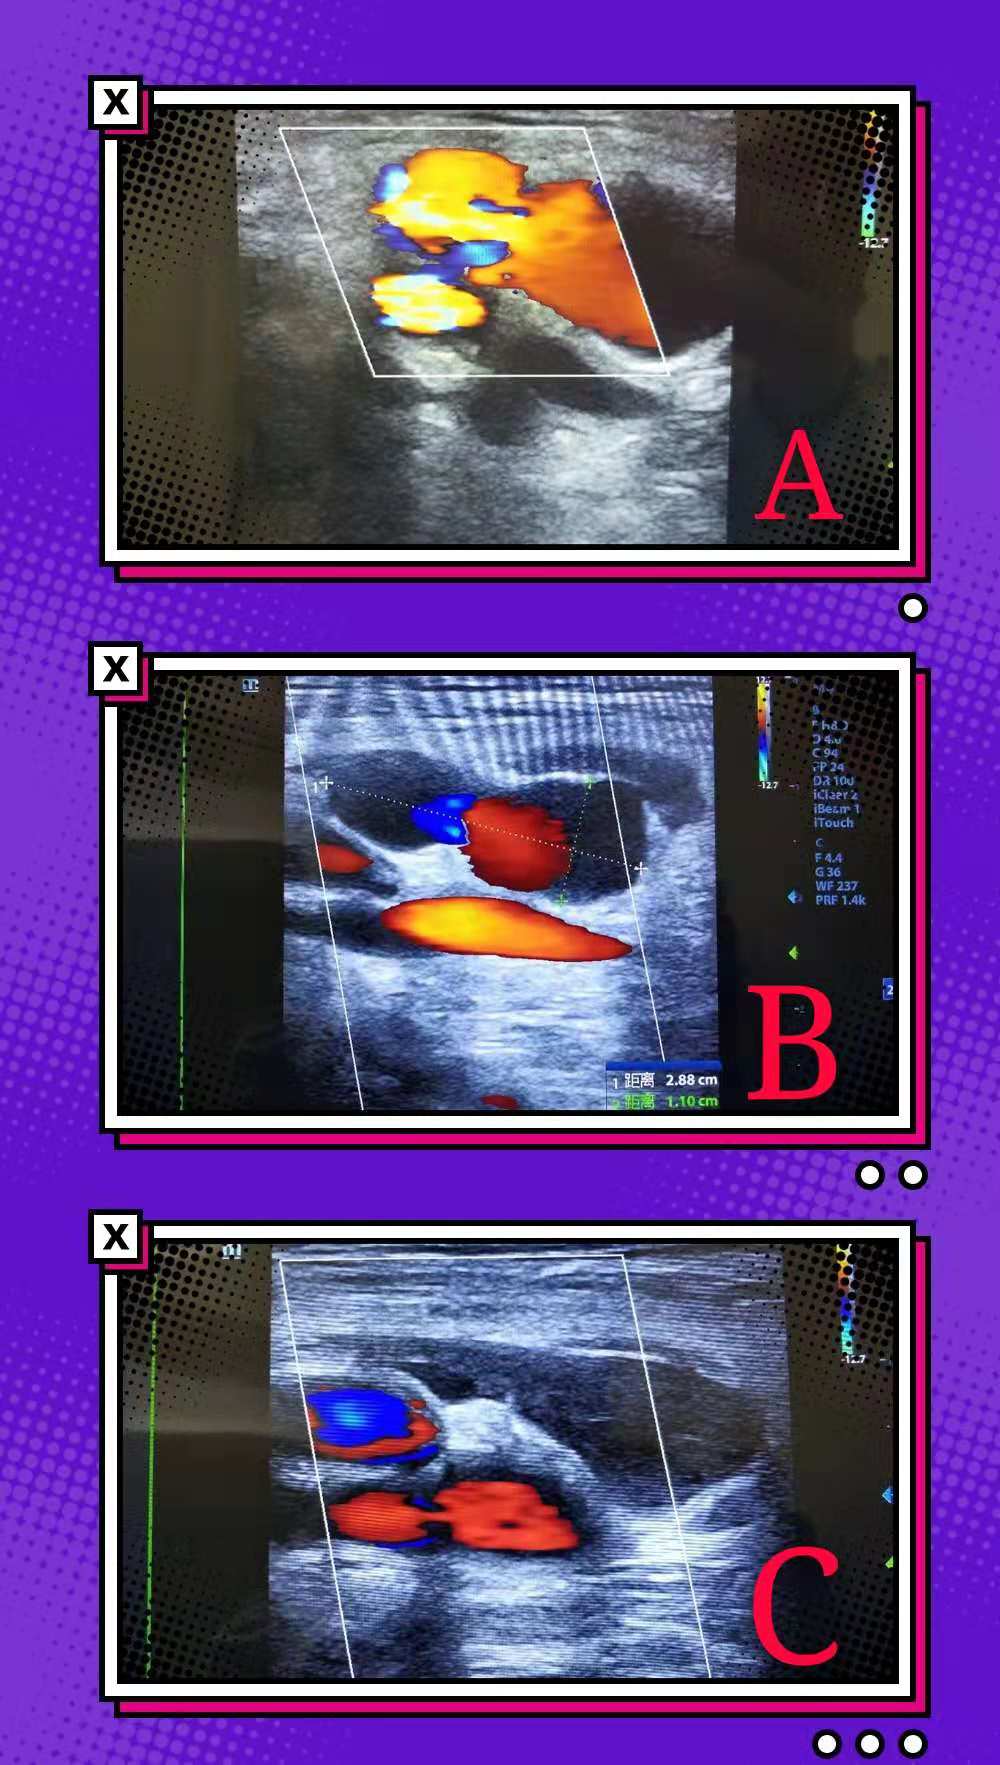

患者李女士, 因双侧下肢动脉血栓病,在中心医院神经内科进行血管扩张术,在术后出现双侧股总动脉假性动脉瘤,经过1天的局部加压包扎后仍未好转,经神经内科医师联合超声科的刘晓晖主任医师、韩婷婷医师商讨后决定为患者行超声引导下经皮假性动脉瘤凝血酶注射治疗术。术中耗费时间仅仅为10分钟。治疗完毕后局部压迫12小时后复查已经完全漏口已经完全闭塞,且患者术前术后生命体征平稳。

随着血管侵入技术的广泛开展,医源性假性动脉瘤的检出率为上升趋势。超声引导下注射凝血酶栓塞治疗假性动脉瘤因其成功率高且并发症发生率极低被广泛应用于临床。其优点主要有:1.成功率高;2.痛苦小,患者容易耐受;3.操作时间短;4.恢复快,复发率极低。对于导管术后采用全身抗凝治疗的患者,栓塞疗法要比加压疗法的成功率高而复发率低。